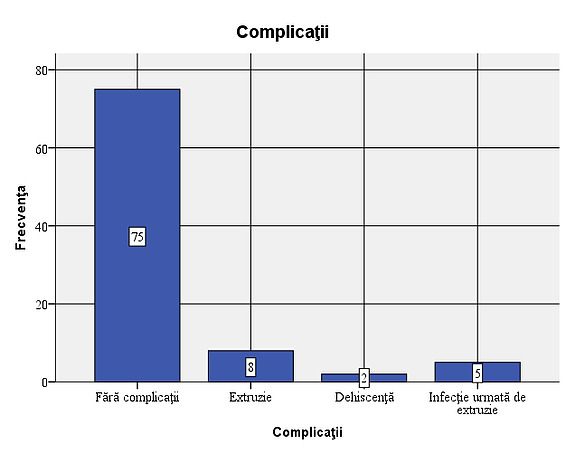

Figure 2: Types of implants used in the sample In 15 of the patients studied (16.7%), complications were observed: 5 cases of infections, 13 cases with extrusions and 2 cases with dehiscence. Out of the total of 15 cases with complications, extrusion occurred in 86.7%. Considering that all cases of infection were followed by extrusion, the situation of complications that occurred is as follows: 8 cases (8.9% of the total number of patients studied) with extrusion only, 5 cases (5.6%) of infection followed by extrusion and 2 cases (2.2%) with dehiscence. In most of the cases with complications, the association of infection with extrusion occurs, dehiscence not being associated with extrusion or infection.

Figure 3: Frequency of complications – 8 cases (8.9% of the total patients studied) with extrusion only, 5 cases (5.6%) of infection followed by extrusion and 2 cases (2.2%) with dehiscence.

- In 15 of the patients studied (16.7%) complications were observed: 5 cases of infections, 13 cases of extrusions and 2 cases of dehiscence. Considering that all cases of infection were followed by extrusion, the situation of complications that occurred is as follows: 8 cases (8.9% of the total number of patients studied) with extrusion only, 5 cases (5.6%) of infection followed by extrusion and 2 cases (2.2%) with dehiscence;